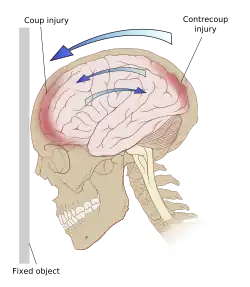

Damage may occur directly under the site of impact, or it may occur on the side opposite the impact (coup and contrecoup injury, respectively).[65] When a moving object impacts the stationary head, coup injuries are typical,[67] while contrecoup injuries are usually produced when the moving head strikes a stationary object.[68]